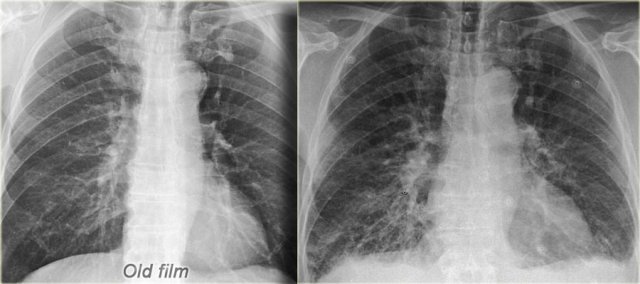

On the left a patient with cardiomegaly and redistribution.

The upper lobe vessels have a diameter > 3 mm (normal 1-2 mm).

Notice the increased artery-to-bronchus ratio at hilar level (arrows).